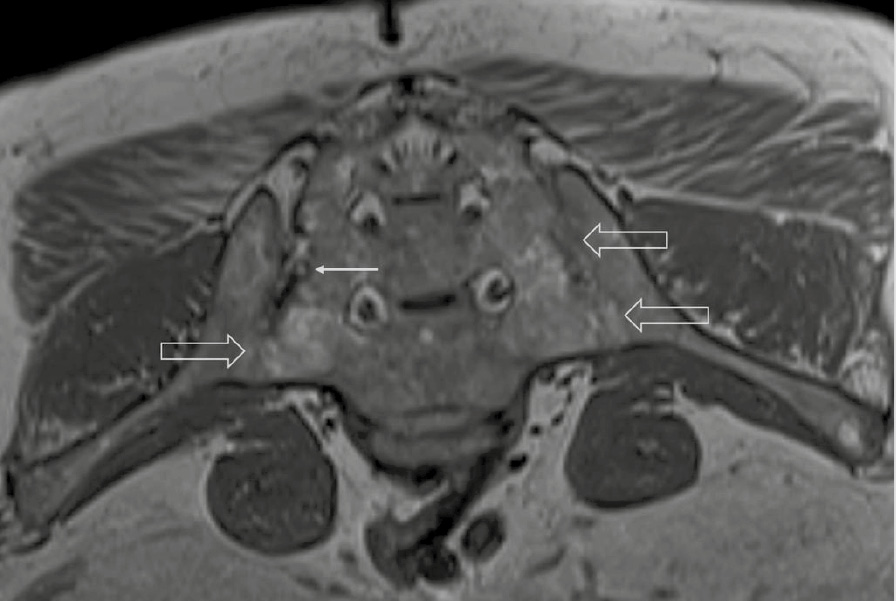

При компьютерной томографии органов грудной клетки данных за «свежие» очаговые и инфильтративные изменения не получено. Увеличения лимфатических узлов подмышечных областей, средостения, корней легких не выявлено. Отмечался усиленный грудной кифоз, обызвествление передней продольной связки, на всем уровне исследования определялись передне-боковые спондилофиты, а также анкилоз большинства реберно-поперечных суставов. По данным рентгенографии кистей (рис. 1, 2) и стоп (рис. 3, 4) диагностированы признаки эрозивного артрита, анкилоз суставов запястья. По данным МРТ крестцово-подвздошных суставов (КПС) определялся неравномерный анкилоз КПС, хрящи по суставным поверхностям неравномерной толщины, примерно на половине протяжении сустава отсутствуют, «суставной промежуток» облитерирован. Неравномерность и нечеткость контура суставных поверхностей за счет множества краевых эрозий справа, единичных – слева, с наличием остеокластоза, в нижнем отделе слева по смежным отделам определяются участки трабекулярного отека, данная находка клинически интерпретирована как двусторонний активный сакроилиит (рис. 5, 6).

Рис. 5. Магнитно-резонансная томография (Т2-взвешенное изображение в поперечной проекции). Протяженные участки анкилоза крестцово-подвздошных сочленений (толстые стрелки), эрозии суставных поверхностей (тонкие стрелки)

Рис. 6. Магнитно-резонансная томография (Т1-взвешенное изображение в косой корональной проекции). Протяженные участки анкилоза крестцово-подвздошных суставов (толстые стрелки), субхондральная киста правой латеральной массы крестца (тонкая стрелка). При магнитно-резонансной томографии крестцово-подвздошных сочленений с обеих сторон определяются крупные зоны анкилоза (суставные щели полностью облитерированы на 1/3 поверхности сустава справа, на 2/3 поверхности слева, что соответствует III рентгенологической стадии сакроилиита справа, IV стадии слева по Келлгрену). На остальных участках суставной хрящ неравномерно истончен, суставные поверхности неровные за счет множественных эрозий справа, единичных – слева. Определяются единичные мелкие (4 мм) субхондральные кисты справа

Ведущим диагнозом в течение всей истории заболевания был «анкилозирующий спондилоартрит, смешанная форма, HLA-B27-ассоциированный», поставленный на основании типичного поражения позвоночника с формированием деформаций (костный анкилоз в переднем отделе Th4 и Th7, множественные синдесмофиты в области передних углов тел позвонков). Заключение МРТ КПС типично для пациента с АС: двусторонний анкилоз КПС, множественные краевые эрозии, с наличием остеокластоза и признаками трабекулярного отека костной ткани, двусторонний сакроилиит. Клиническая картина, проявляющаяся болями воспалительного характера и скованностью в пояснично-крестцовом отделе позвоночника, нарушением объема движения в позвоночнике, была характерна для прогрессирования АС. Диагноз подтверждался наличием положительного гена HLA-B27 [2].